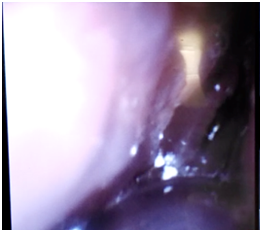

Intravenous fentanyl was administered, after a suitable latency period, the flexible fibroscope was introduced through the oral cavity. The patient maintained spontaneous ventilation and after locating glottis cleared by abundant tumor tissue (Figure 8), simple lidocaine 2% 40 mg was installed at the glottis level and once the vocal cords were passed with the fibroscope before the visualization of tracheal rings and tracheal carina, the endotracheal tube of small diameter was introduced.

Figure 8